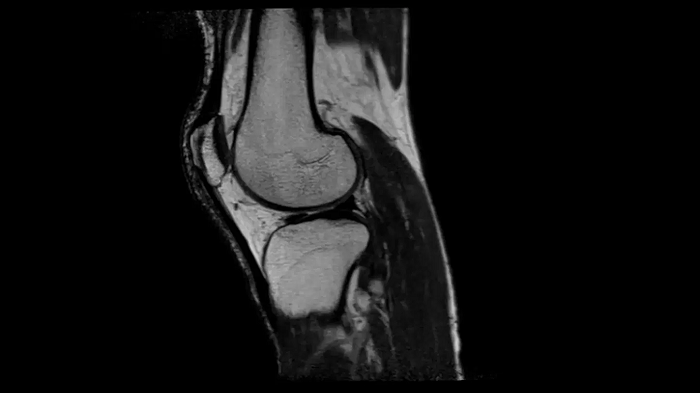

3D MSK Imaging with Compressed Sensing

Knee imaging with T2w SPACE can be expedited using Compressed Sensing to reduce acquisition times, offering high-resolution images for uncompromised knee assessments.

Compressed Sensing 6

0.3 x 0.3 x 0.6 mm2

TA 4:15 minutes

MAC-ID: 7aaaa0175. Image Credit: Siemens Healthineers